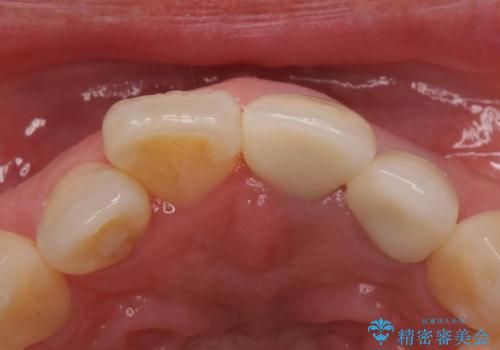

- 左上12 : 仮歯 / 11,000円×2、ジルコニアクラウン(スタンダード) / 121,000円×2 合計264,000円費用は治療当時の料金となります

色調はクラウン修復により改善され、歯並びも術前より改善されたことで大変喜んでいただけました。